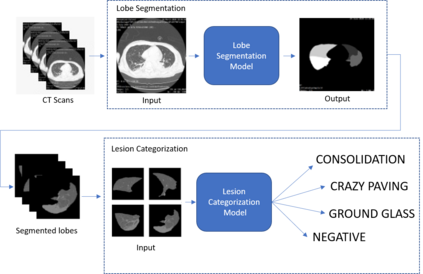

COVID-19 infection caused by SARS-CoV-2 pathogen is a catastrophic pandemic outbreak all over the world with exponential increasing of confirmed cases and, unfortunately, deaths. In this work we propose an AI-powered pipeline, based on the deep-learning paradigm, for automated COVID-19 detection and lesion categorization from CT scans. We first propose a new segmentation module aimed at identifying automatically lung parenchyma and lobes. Next, we combined such segmentation network with classification networks for COVID-19 identification and lesion categorization. We compare the obtained classification results with those obtained by three expert radiologists on a dataset consisting of 162 CT scans. Results showed a sensitivity of 90\% and a specificity of 93.5% for COVID-19 detection, outperforming those yielded by the expert radiologists, and an average lesion categorization accuracy of over 84%. Results also show that a significant role is played by prior lung and lobe segmentation that allowed us to enhance performance by over 20 percent points. The interpretation of the trained AI models, moreover, reveals that the most significant areas for supporting the decision on COVID-19 identification are consistent with the lesions clinically associated to the virus, i.e., crazy paving, consolidation and ground glass. This means that the artificial models are able to discriminate a positive patient from a negative one (both controls and patients with interstitial pneumonia tested negative to COVID) by evaluating the presence of those lesions into CT scans. Finally, the AI models are integrated into a user-friendly GUI to support AI explainability for radiologists, which is publicly available at http://perceivelab.com/covid-ai.